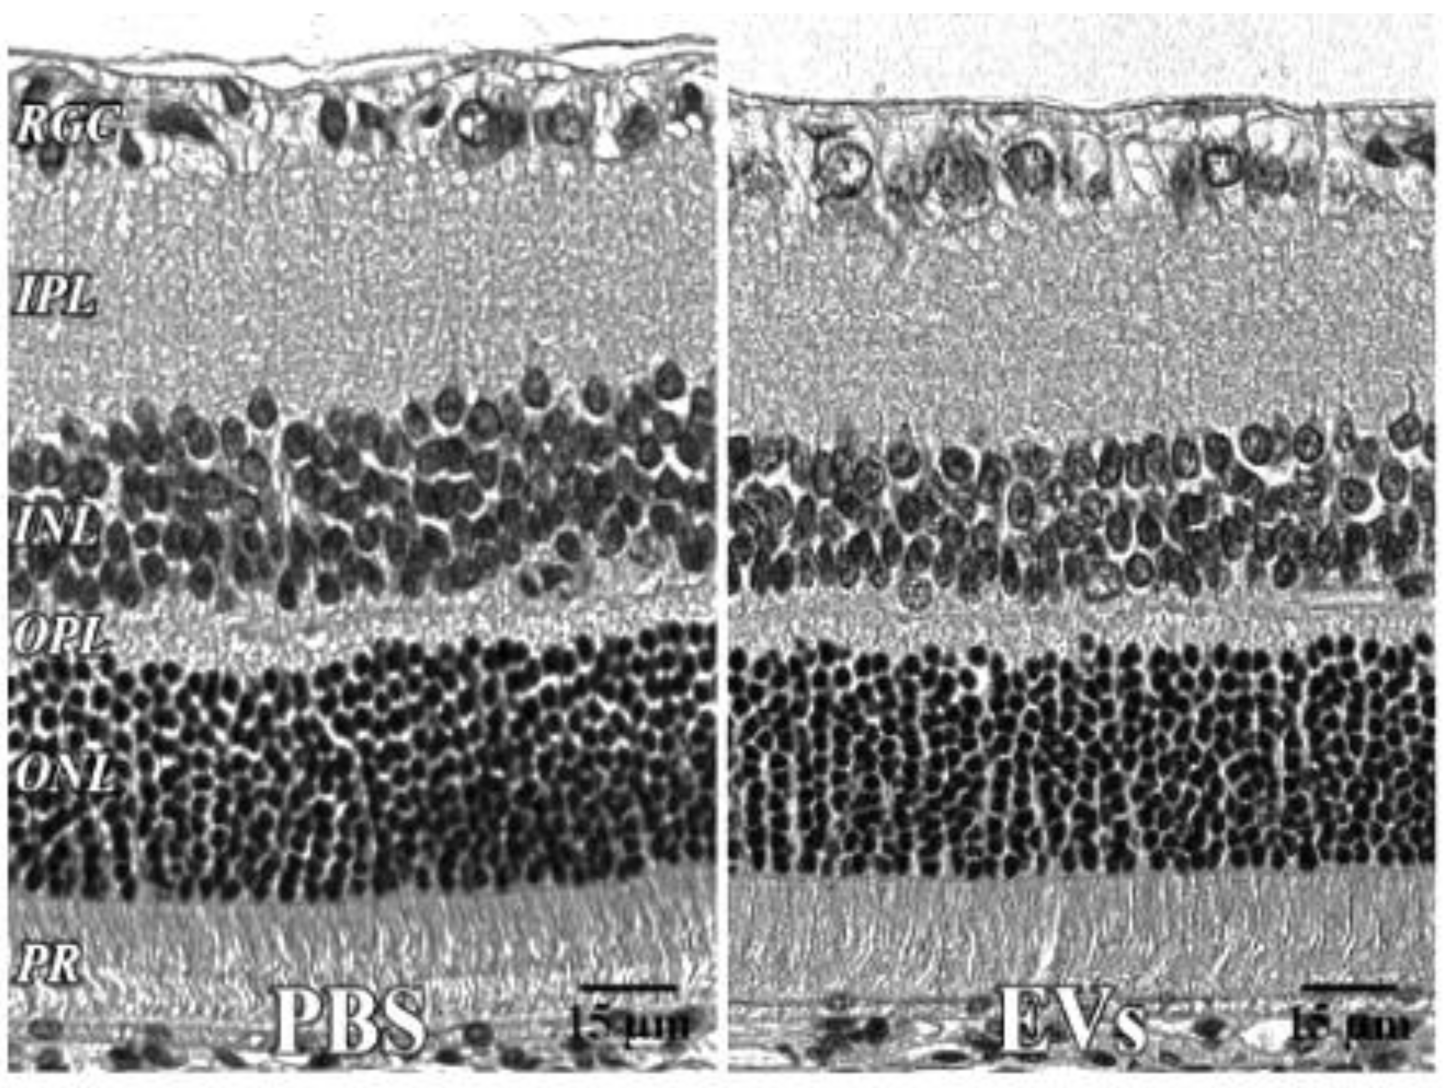

Figure 5.

Retinal histology after intravitreal EVs. PBS—injected eye left; EV—injected right, both 7 days after injection, with no significant change in retinal cell layer thicknesses. 40x. RGC = retinal ganglion cell layer; INL = inner nuclear layer; IPL = inner plexiform layer; OPL = outer plexiform layer; ONL = outer nuclear layer; PR = photoreceptor layer. Scale bars (with black lettering, 15 μm) are on bottom right of each panel.

Retinal histology after administration of EVs. For the EV toxicity study, histological sections (Figure 5) were stained with hematoxylin and eosin (H and E). One eye received PBS, the other EVs. N = 5. There were no significant changes in retinal layer thicknesses, measured in μm. IPL = inner plexiform layer, OPL = outer plexiform layer, SEM = standard error of the mean.